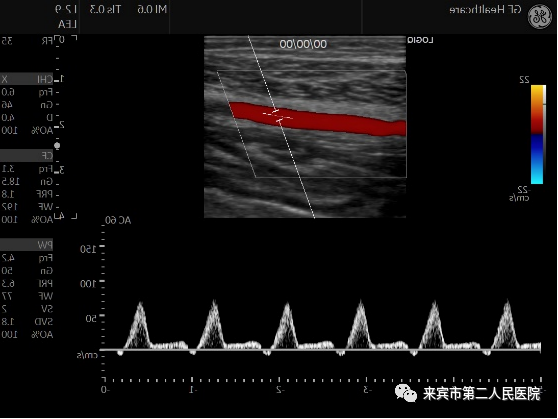

二、彩超在血管检查中的应用:

彩超可以对人体的颅内外动静脉,心血管以及四肢动静脉进行检查,应用彩色多普勒可以检测到颅内血管内血流速度,以此判断有无血管痉挛或者是血管狭窄。

通过对颈部血管的检测,可以清晰地显示出颈部动脉壁是否增厚、斑块、血栓、狭窄、闭塞等等,而通过对四肢血管检测,可以检查出动脉有无狭窄、闭塞以及血流的速度,可以排除四肢静脉有无血栓形成,以及有无瓣膜功能不全、反流等等情况。

2.从多个维度观察血管、组织的血流灌注,明确诊断,CDFI彩色及PDI能量多普勒。